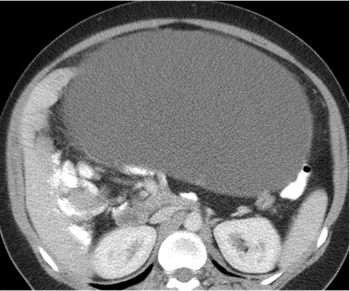

Mucinous cystadenom: 33-year-old female with abdominal distension and suspected ovarian mass. CT scan of abdomen and pelvis done with oral and intravenous contrast with multiple axial sections along with coronal and sagittal reformation.